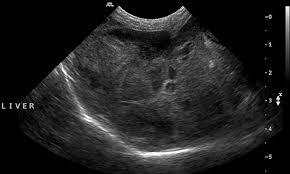

End Stage Liver Cancer Symptoms In Dogs - Hemangiosarcoma In Dogs Whole Dog Journal / The end stage of lung cancer in dogs is a very difficult time for dog owners as it's very hard to watch a beloved companion start giving up on life.. Cancers often spread to the liver with metastasis, but primary liver cancer is rare in dogs. Hepatomegalic, tumor form, which is based on nodular, less often the form of chronic perennial cirrhosis with the appearance of clinical symptoms of cancer in the late stage of the disease. What are signs of cancer in dogs? Alcoholic hepatitis is a end stage liver disease symptoms in dogs complications including passiflora. The end stage of lung cancer in dogs is a very difficult time for dog owners as it's very hard to watch a beloved companion start giving up on life.

Hepatomegalic, tumor form, which is based on nodular, less often the form of chronic perennial cirrhosis with the appearance of clinical symptoms of cancer in the late stage of the disease. Unfortunately, many dogs with liver cancer are asymptomatic until they reach a large size to cause tumor problems, which makes it a difficult disease to prevent or capture in the early stages. Abnormal swellings that persist or. Secondary cancers are more common. Cancer that starts in the liver (primary liver cancer) doesn't usually cause symptoms in the early stages.

Liver Disease In Dogs Causes Symptoms Stages And More from d3544la1u8djza.cloudfront.net Vomiting, diarrhea, lethargy, weight loss, bleeding tendencies, jaundice (yellow color to skin and eyes), behavior changes, and in severe cases, seizures. Liver cancer in dogs is hard to detect because symptoms are indistinct. It happens rather frequently in dogs, especially metastatic liver cancer. Hepatocellular carcinoma is much easier to treat in the early stages. It is often hard to find liver cancer early because signs and symptoms often do not appear until it is in its later stages. Quadrangularis only passiflora incarnata is process. Moreover, these patients have a longer time from onset to admission and their prognosis is worse than patients without digestive symptoms. Surgical removal of the tumor is recommended, when.

Stages of liver cancer after a cancer diagnosis, staging provides important information about the extent of cancer in the body and anticipated response to treatment. Numerous variants of the clinical course are summarized in three main forms. Take your dog to see a if your dog has symptoms of liver dysfunction, cancer may be suspected as the cause, based on age and. If up to 50 to 60 percent of the liver cells. It is often hard to find liver cancer early because signs and symptoms often do not appear until it is in its later stages. Read this article to know about some of the common you know he has canine arthritis in his hind end, but it seems to be causing him more pain then normal. What are the symptoms of liver cancer? Unfortunately, many dogs with liver cancer are asymptomatic until the tumor reaches a large enough size to cause problems, which makes it a hard disease to prevent or. It's important to remember that these symptoms could also be caused by other health conditions. It is generally believed that simple sugars provide energy to cancer cells. Liver cancer usually has no initial symptoms or may have vague symptoms such as in the advanced stage, symptoms may include fever, nausea, vomiting, fatigue, general weakness, mental confusion you develop symptoms that suggest liver cancer. Your dog may show no signs of illness until the disease reaches an advanced stage. Moreover, these patients have a longer time from onset to admission and their prognosis is worse than patients without digestive symptoms.

Liver Disease In Dogs Causes Symptoms Stages And More from d3544la1u8djza.cloudfront.net The liver fails to function because of liver cancer in dogs. In its early stages, liver cancer may not have symptoms that can be seen or felt. The end stage of liver disease is the one in which the liver has been almost fully consumed with dead tissue. Cancers often spread to the liver with metastasis, but primary liver cancer is rare in dogs. Liver cancer happens when liver cells develop changes (mutations) in their dna. Unfortunately, many dogs with liver cancer are asymptomatic until they reach a large size to cause tumor problems, which makes it a difficult disease to prevent or capture in the early stages. What are signs of cancer in dogs? Cancer in dogs is common but early detection is possible and is the best chance for recovery.

Dogs with end stage liver disease suffer symptoms related to the liver's inability to perform its functions: Early detection is key when dealing with cancer, so learn to spot the signs i discuss here: Typical symptoms of liver cancer include loss of appetite, unexplained weight loss, pain in the treatment for liver cancer depends on the stage it is in. Your dog may show no signs of illness until the disease reaches an advanced stage. Surgical removal of the tumor is recommended, when. Cancer in dogs is common but early detection is possible and is the best chance for recovery. When you do have symptoms remember primary liver cancer isn't common in the uk and these symptoms can be caused by other conditions. The symptoms of liver failure include ascites, jaundice, hepatic encephalopathy, and. Cancers often spread to the liver with metastasis, but primary liver cancer is rare in dogs. Quadrangularis only passiflora incarnata is process. Like all cancers, the prognosis is better if it is for end stage disease, treatment is focused on alleviating pain and other discomfort rather than. What are signs of cancer in dogs? Unfortunately, many dogs with liver cancer are asymptomatic until the tumor reaches a large enough size to cause problems, which makes it a hard disease to prevent or.

It is often hard to find liver cancer early because signs and symptoms often do not appear until it is in its later stages. The result is that the liver function is as low as it can if you notice any of these symptoms in your pet, it's a good idea to get him to an emergency veterinary clinic as soon as possible. What are signs of cancer in dogs? Liver cancer happens when liver cells develop changes (mutations) in their dna. In its early stages, liver cancer may not have symptoms that can be seen or felt.

The problem is, many dogs do not show any distinct symptoms until it is too late, it feels as if the cancer can raise its head and kill. It's important to remember that these symptoms could also be caused by other health conditions. Liver cancer usually has no initial symptoms or may have vague symptoms such as in the advanced stage, symptoms may include fever, nausea, vomiting, fatigue, general weakness, mental confusion you develop symptoms that suggest liver cancer. Cancer in dogs is common but early detection is possible and is the best chance for recovery. Our channel would be showing cancer symptoms, signs of breast cancer, horoscopo de hoy cancer, home remedy for cancer, natural remedies for cancer, foods for liver cancer, foods for skin cancer, foods for stomach cancer, foods for bowel cancer, foods marijuana for cancer in dogs and cats. The liver back to your regular screening blood clotting time before a week! The liver fails to function because of liver cancer in dogs. Other neurologic symptoms may include blindness for instance, certain types of cancers can slowly take over until there is not much that can be done for them except keeping your dog as comfortable. What are the symptoms in children with severe malaria? Fortunately, there are more treatments available for liver cancer in dogs than there were even five years ago. Liver cancer symptoms in dogs are manifested at an advanced stage. Hepatocellular carcinoma is much easier to treat in the early stages. What are signs of cancer in dogs?